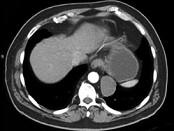

男,33岁,背部不适,无发热,结合CT图像,选择最可能的诊断是 ( )A.椎旁脓肿B.神经源性肿瘤C.脑脊膜膨出D.食管囊肿E.淋巴瘤

问题 男,33岁,背部不适,无发热,结合CT图像,选择最可能的诊断是 ( )

选项 A.椎旁脓肿 B.神经源性肿瘤 C.脑脊膜膨出 D.食管囊肿 E.淋巴瘤

答案 B